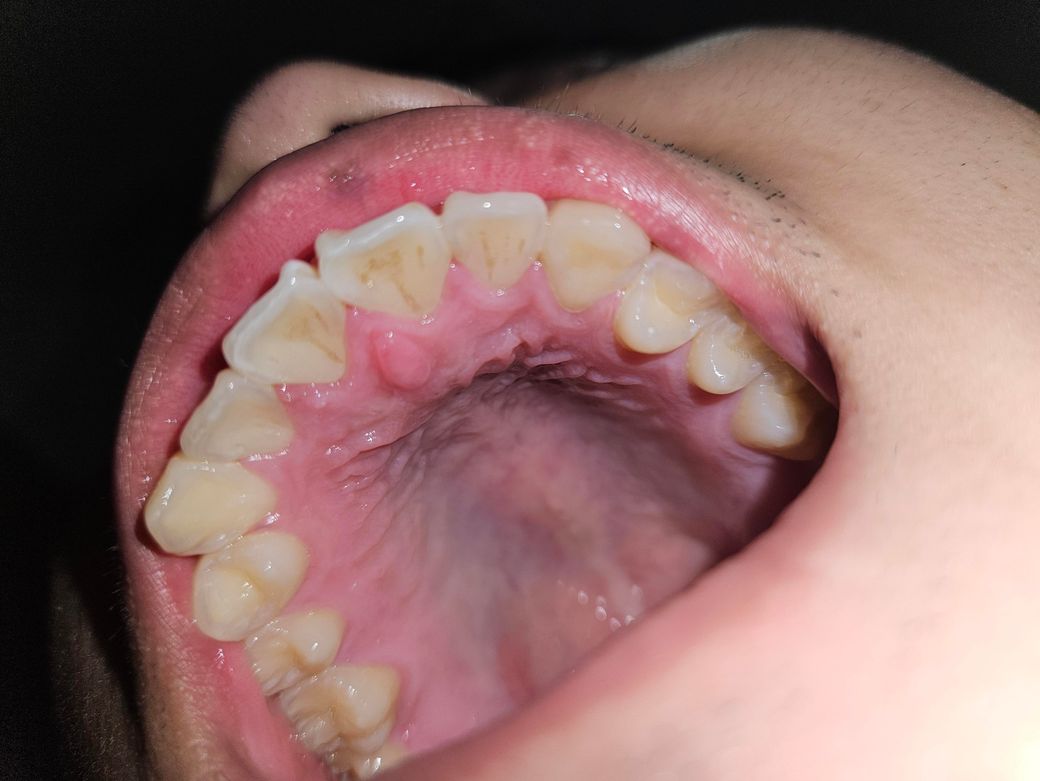

윗 이빨이랑 아랫 이빨이 이상하게 맞다아서 이상한 느낌이에여.. 갑자기 왜이러는걸까여?

어제부터 갑자기 이상한 느낌이 들는 겁니다. 느낌이 이상한데 왜이러는걸까여? 느낌도 이상해서 신경이 자꾸 자꾸 쓰이네요... 왜이러는 걸까여?

교합을 보기 위해서는 사진으로는 어렵습니다. 단지 해당 사진을 보면 위쪽 앞니 입천장의 치간 유두 부위가 부어 있습니다. 이건 감염일 수도 있으나 단순 위생관리가 부족해서 그런 경우도 있습니다. 일단은 치과에서 스케일링을 한번 받아보시고 증상 개선이 있는지 보시기 바랍니다.